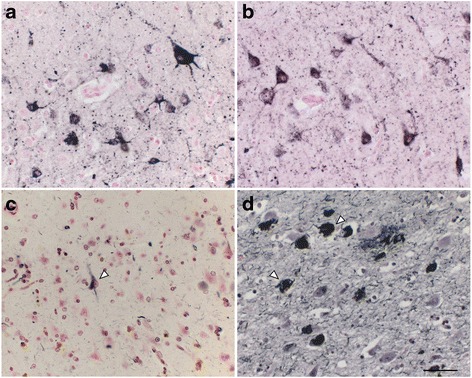

We observed numerous AT8-positive processes (Fig. 3a, dark purple, arrowheads), independent of Aβ (Fig. 3a, brown, asterisk) in the temporal cortex. Similar structures in the same area were positive exclusively for RD4 (Fig. 3b) and oriented around blood vessels (Fig. 3b, arrows). Thorn-shaped astrocytes or granular/fuzzy astrocytes grouped under the umbrella of “aging-related tau astrogliopathy” were not apparent in these monkey brains [ref. 22]. AT8-positive oligodendroglia-like cells and threads were abundant in GP (Fig. 4a) and in the white matter (Fig. 1e). Both perikarya and threads of these oligodendroglia-like cells were positive for both Gallyas silver impregnation (Fig. 4b), and RD4 (Fig. 4c) in adjacent sections, but consistently negative for 3R (Fig. 4d). In summary, AT8/RD4-positive neurons were pretangle-like but their distribution was accentuated in pyramidal neurons of Ammon’s horn (Fig. 1a and f arrow) as in AD. However, AT8/RD4-positive glial cells in the hippocampal white matter (Fig. 1a, d and f asterisks) and basal ganglia were conspicuous.

Tau-positive lesions were particularly numerous in the oldest monkey examined (36 yo Fig. 1). However, these cytopathological findings, including pretangle forms of tau in neurons, tau-positive astrocytes, and inclusions in oligodendroglia-like cells, were also detected in brain sections from other monkeys older than 30 years of age (Fig. 5). Similar to the 36-year old monkey, tau-positive lesions were seen more frequently in the neocortex than in the hippocampus (Fig. 5).

In all brains examined in this study, tau-positive structures exhibited immunoreactivity for 4R, but not 3R tau. Tau-positive structures were also argyrophilic with Gallyas, but not with Campbell-Switzer silver impregnation. This cytopathology is different from that of AD, which usually exhibits immunoreactivity for both 3R and 4R tau, and argyrophilia with both Gallyas and Campbell-Switzer silver impregnations [ref. 19]. Instead, these phenotypes suggest that a PSP or CBD-like cytopathology may occur in brains of aged primates. Supporting this idea, the 4R-positive structures that we identified around blood vessel in old primates (Fig. 3b) are similar to tau-positive structures identified in tuft-shaped astrocytes in PSP and astrocytic plaques in CBD [ref. 25]. Further, we did not observe tau IR in neurites around senile plaques (Fig. 3a, asterisk), suggesting that most tau-positive structures in old primate brains may be of glial origin similar to human PSP/CBD, which are not frequent in aged human brains with AD pathologies. Moreover, these tau-positive astrocytes are morphologically different from thorn-shaped astrocytes, granular/fuzzy astrocytes grouped under the umbrella of “aging-related tau astrogliopathy [ref. 22]” Consistent with our results, Kiatipattanasakul and colleagues [ref. 26] previously described PSP-like tau deposition in neurons and glia in an aged (35 yo) albino cynomolgus monkey. They also observed Gallyas-positive glia in the basal ganglia, thalamus, brainstem and the white matter as well as NFTs in the thalamus. However, they proposed that the occurrence of PSP-like cytopathology in their monkey brain was exceptional. In our study, however, we observed similar neuronal and glial cytopathological alterations of tau in 5 out of 7 monkeys over 30 years of age (Table 2, Fig. 5), suggesting that PSP-like cytopathologies may instead represent a common aspect of aged monkey brains.

Although tau-positive lesions were found in temporal and hippocampal areas in the oldest monkey examined (36 M, Fig. 1), lesions were also abundant in the white matter and basal ganglia, predominantly in oligodendroglia-like cells and as intrafascicular threads. In other monkeys over 30 years of age, lesions were present in the frontal and temporal neocortices and basal ganglia rather than in the hippocampus (Fig. 5). Again, this distribution of tau-positive lesions is reminiscent of the aged cynomolgus monkey described by Kiatipattanasakul et al. [ref. 26], and suggest cytopathological alterations characteristic of PSP rather than those of AD [ref. 10, ref. 13]. A similar cortical distribution of tau lesions, different from human AD, has been reported in the brains of gorilla [ref. 14, ref. 15]. Taken together, tau-positive lesions in aged non-human primate brains do not necessarily represent AD-like pathogenesis even though Aβ deposits may be present in the same specimens.